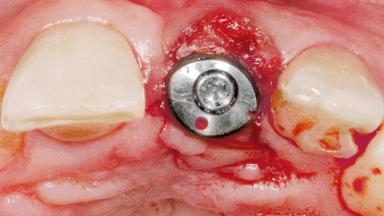

A 39-year-old male patient presented with a chief complaint of discomfort and gingival discoloration around his maxillary left central incisor. He was in good general health and was a non-smoker. His past dental history was significant because of the traumatic fracture of tooth 21 in a sporting accident at age 13. Initial dental treatment included endodontic therapy and a full-coverage restoration. The patient became symptomatic 5 years later, when structural failure of the tooth resulted in the dislodgment of the crown. Endodontic retreatment, apical surgery, and post-and-core restoration were performed.

| Placement Protocol | Early or late implant placement |

| Bone Volume | Deficient horizontally, requiring prior grafting |